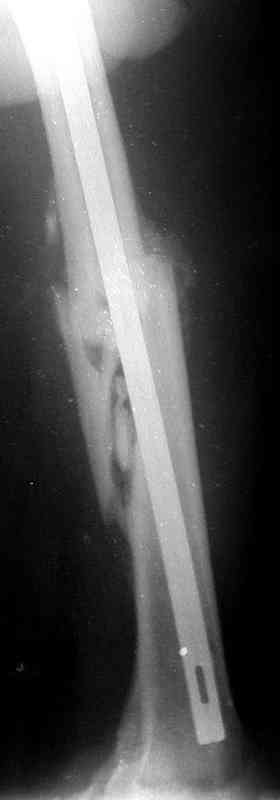

Уважаемые коллеги!На прилагаемых снимках - состояние после оперативного вмешательства (открытый перелом левого бедра в средней трети):

МОС, стержень нефиксированный. С момента операции прошло 8 месКак по Вашему мнению происходит консолидация? Допустимо ли смещение или необходима повторная операция по выравниванию конечности? Если да, какой метод рекомендуете (фиксированный стержень, пластина)?Буду благодарен за оперативный ответ.

При таком диаметре штифта не удивительно, что перелом не сросся (кстати, какой диаметр и что за модификация штифта?).

Вчера, когда написал свое сообщение, решил еще раз открыть фоторентгенограмму и убедиться в правильности своих суждений на счет общепринятого интрамедуллярного остеосинтеза. Попытка была безуспешна:)

Сегодня фотография открылась...беру свои слова назад: перелом явно в расширенном участке бедра. Целесообразней всего динамический блокирующий остеосинтез.

Ротации конечности у больного нет?